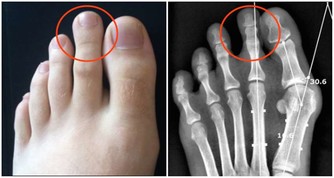

第一次手術我的左側甲狀旁腺就被拿掉了,但是我不知道,醫生也沒有醫囑。在那個年代也沒有補鈣的概念的。我記得大肆廣告補鈣是在95、96年,我87年做的手術時可沒人給我說過這個事情。幸好我右側的甲狀旁腺保留了,它的功能也有了代償。所以沒有發生過抽搐等現象。但是其實身體是出於缺鈣的症狀的,我的腳趾甲就沒長起來,只有兩個大腳趾有指甲。

萬幸我的個子是長起來了,165cm,算是中等個了。由於無知,上大學時偷偷停了半年的藥,我就是不想終生服藥,想看看停藥有什麼不行的。半年後,甲減的症狀越來越明顯了,出現了思維跟不上的情況,明顯反應遲鈍。更壞的結果很快就來了,在一次體育跳遠課上輕輕的一跳,就跳成了左腿脛骨粉碎性骨折,打了一個月石膏。後來經過一年的康復鍛煉,腿才又恢復了。我從骨折後有開始恢復服甲狀腺素片了。甲狀腺癌復發有可能是從那時開始的。